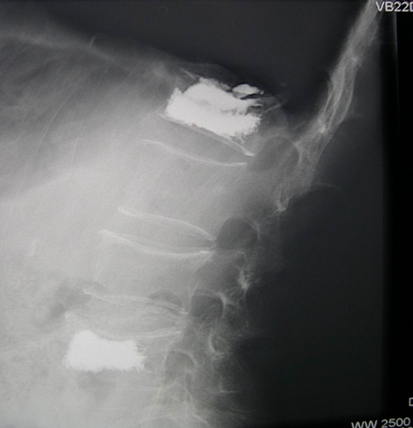

X线片上往往不能判断脊柱骨折处于骨质愈合的哪个阶段多椎体的骨折可能发生于不同时期,并非每个被压缩椎体都是责任椎体,需要手术治疗MRI在判断骨折椎体是否愈合及选择手术椎体时起重要作用急性期或亚急性期(2-30天之间的骨折):T1WI呈低信号, T2WI呈高信号晚期(30天以后):T1WI和T2WI上表现等信号。

当椎体T1WI、T2WI无信号改变,即使X线片椎体有压缩改变,亦说明椎体骨折已愈合,椎体已处于稳定状态,为非责任椎体,可不予治疗。相反对于X线片椎体无明显压缩,但MRI有显著信号改变者应考虑为责任椎体,予以手术。

侧位:针尖至椎弓根的1/2;正位:针尖位于椎弓根影的中线处侧位:针尖至椎体后缘;正位:针尖位于椎弓根的内侧缘侧位:针尖至椎体前中1/3交界处;正位:针尖位于椎体中线略偏对侧

注射的过程应在透视监测下进行,当骨水泥到达椎体后1/5时应减慢注射速度,一旦发现骨水泥到达椎体后缘时应立即停止注射。